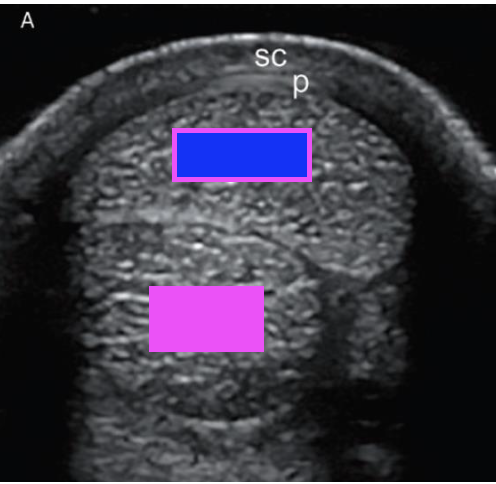

what structure does the pink box indicate?

deep digital flexor tendon

what structure does the blue box indicate?

superficial digital flexor tendon